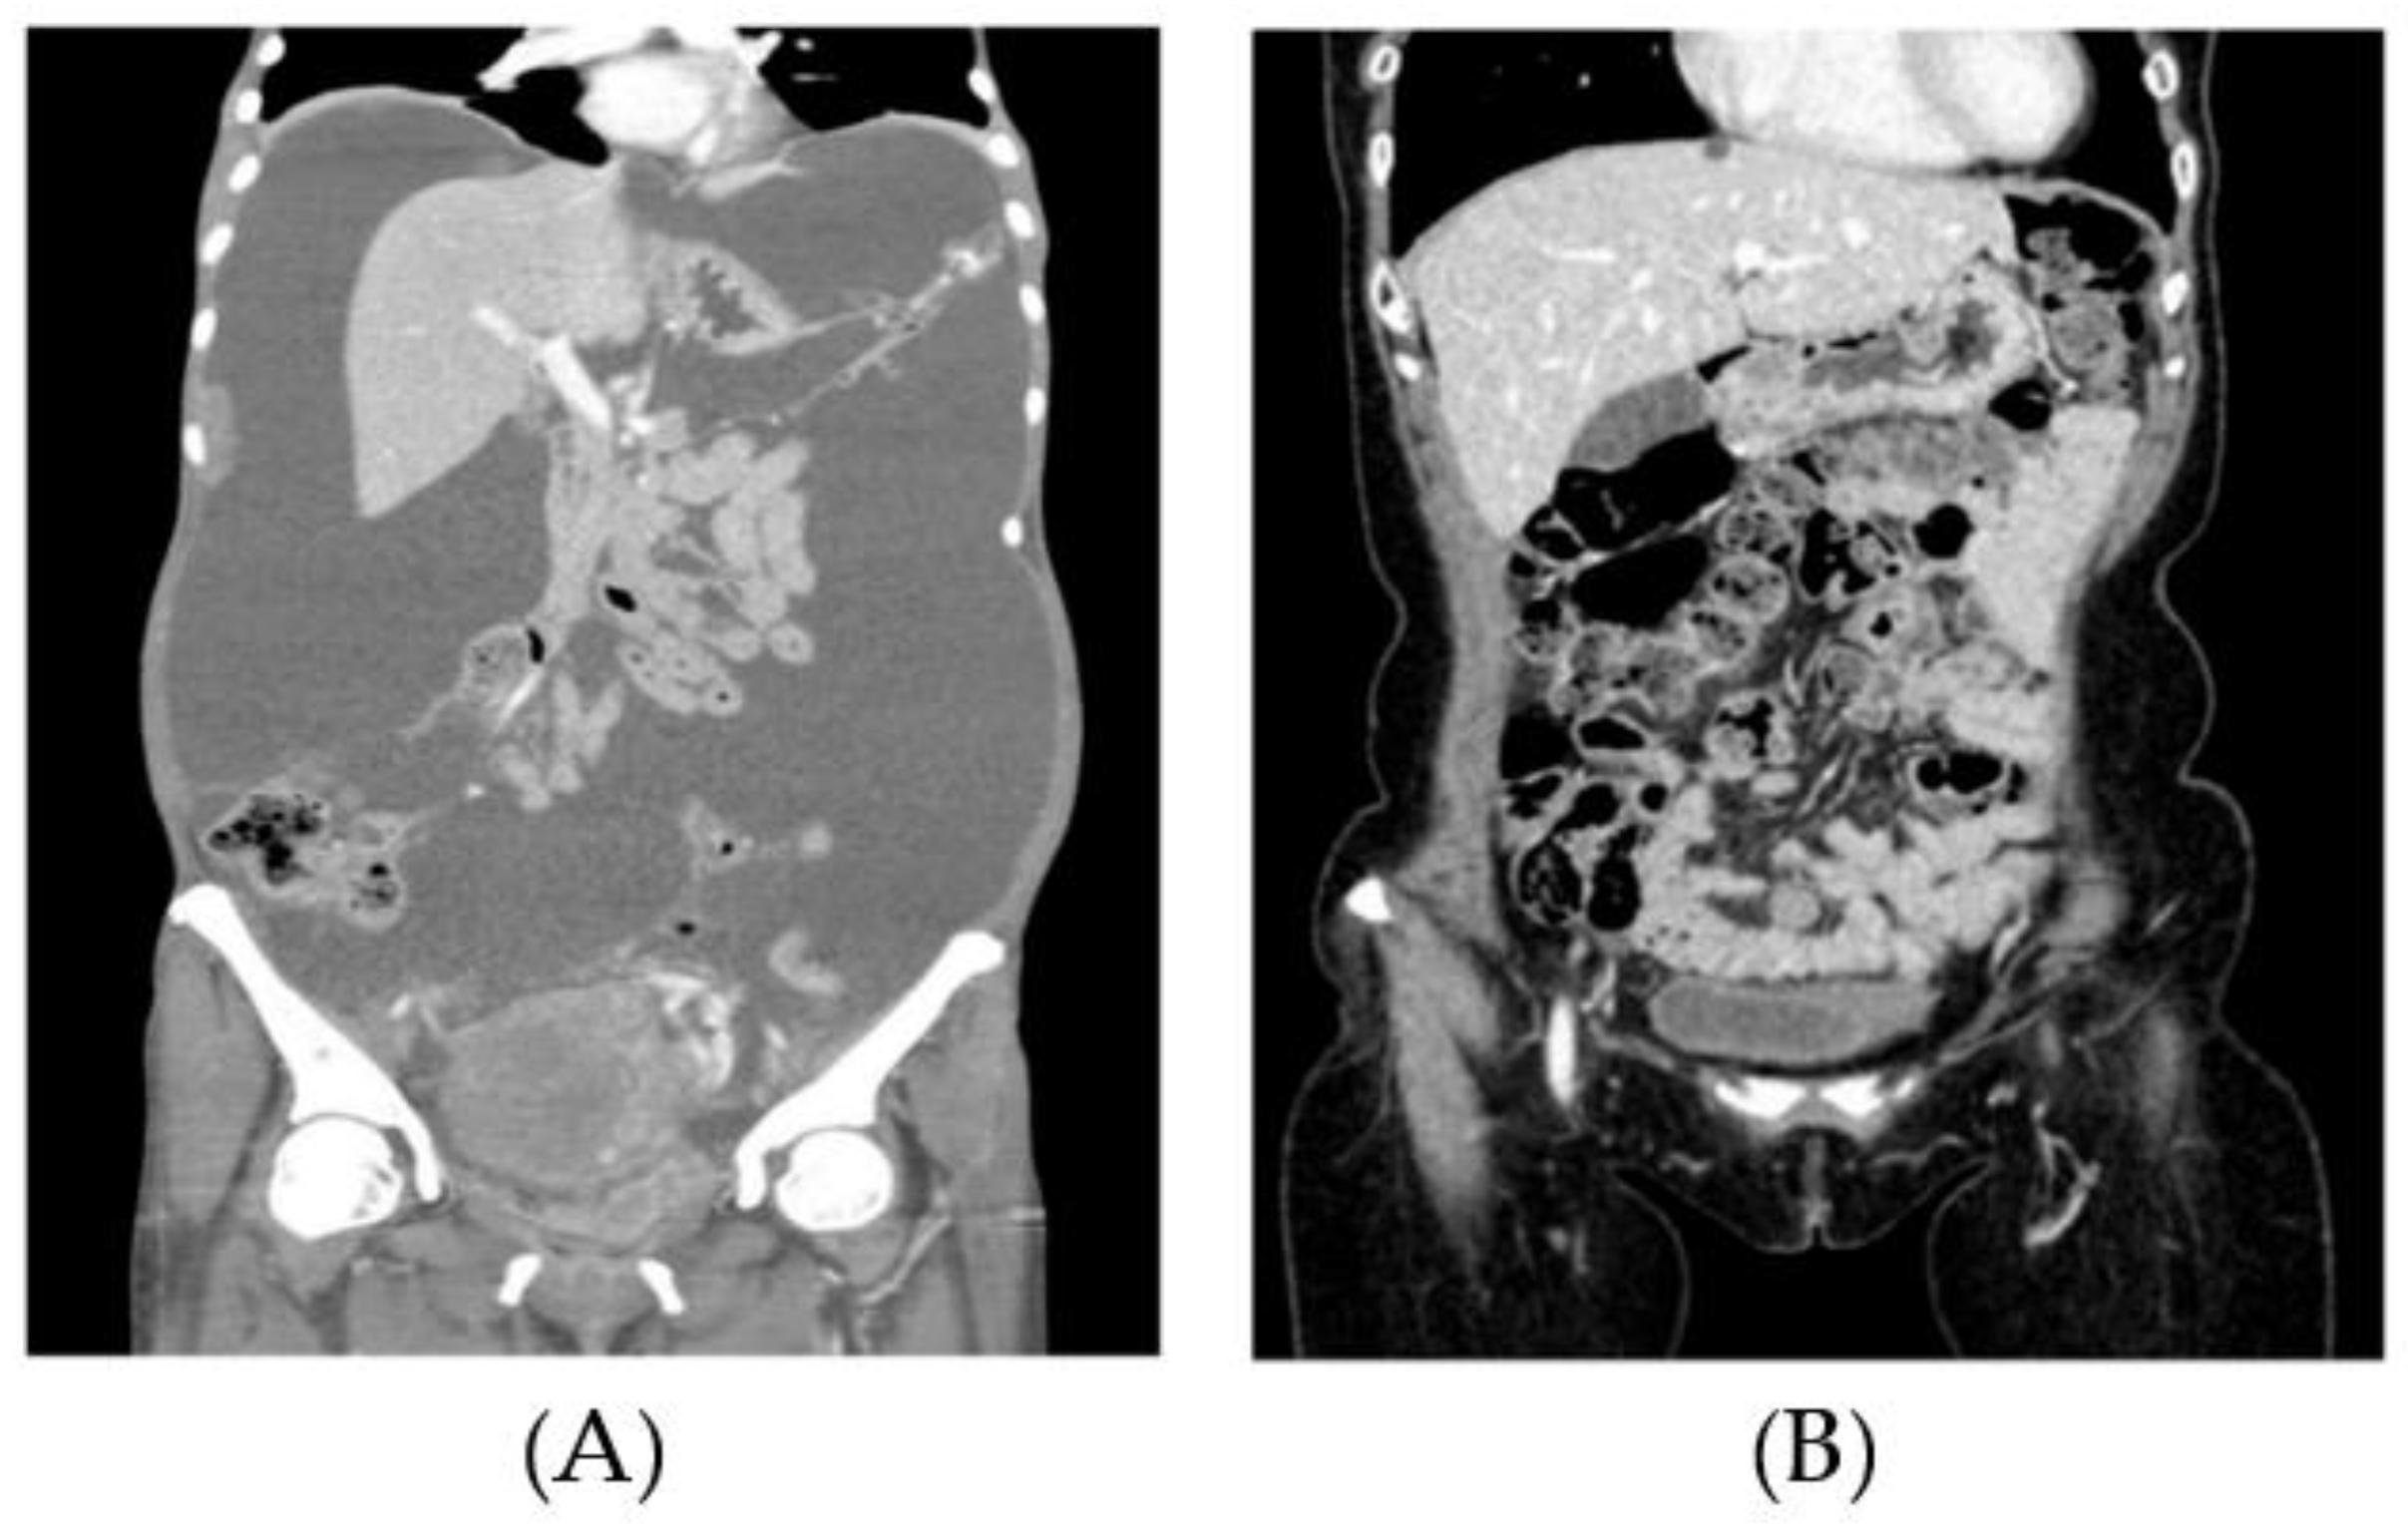

7. Clinical Applications of High Doses of Sodium Selenite (Cancer Studies)